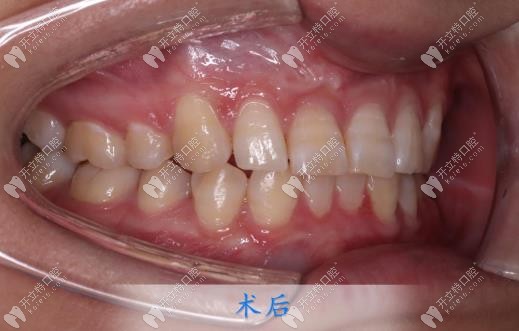

跑偏了,取下牙套后,牙齒的情況已經(jīng)全部改善了。但更讓我開心的是我的下巴,之前因?yàn)樽彀蛯?dǎo)致下巴不明顯,矯正后下巴竟然有了,顏值也改變了好多,朋友見我都說我變好看了,但是又說不出來哪里變了!

都說牙齒矯正做好了堪比整容,我以前是真不信這句話的,直到自己親身經(jīng)歷,還是想給小伙伴們提個醒:找個認(rèn)真且負(fù)責(zé)的正畸醫(yī)生,真的可以省去好多麻煩!